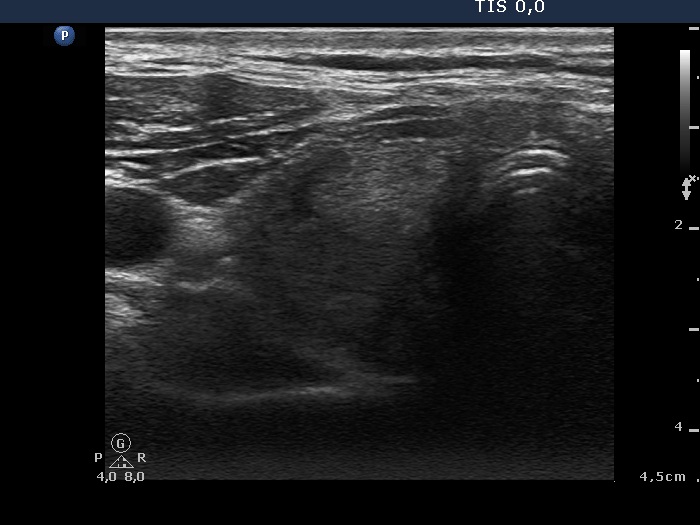

Right lobe, longitudinal scan

Right lobe, another transverse scan. The lesion presents halo sign.